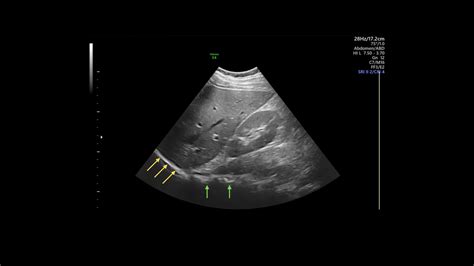

Interpreting the results of a liver ultrasound involves assessing the images for any abnormalities. A normal liver ultrasound will show:

• Size and Shape: The liver should be of normal size and shape, with smooth edges.

• Echogenicity: The liver tissue should have a uniform echogenicity, indicating a healthy structure.

• Blood Flow: Normal blood flow through the liver and its vessels.

• Absence of Abnormalities: No cysts, tumors, or other abnormalities should be present.

While a normal liver ultrasound is the desired outcome, there are several common findings that may be detected during the procedure. These include:

• Fatty Liver Disease: Excess fat accumulation in the liver, which can be benign or indicative of more serious conditions like non-alcoholic fatty liver disease (NAFLD).

• Cysts: Fluid-filled sacs that can form in the liver. Most cysts are benign and do not require treatment.

• Tumors: Abnormal growths that can be benign or malignant. Further testing is usually required to determine the nature of the tumor.

• Hepatitis: Inflammation of the liver, often caused by viral infections or autoimmune disorders.

• Cirrhosis: Advanced liver disease characterized by scarring and loss of liver function.